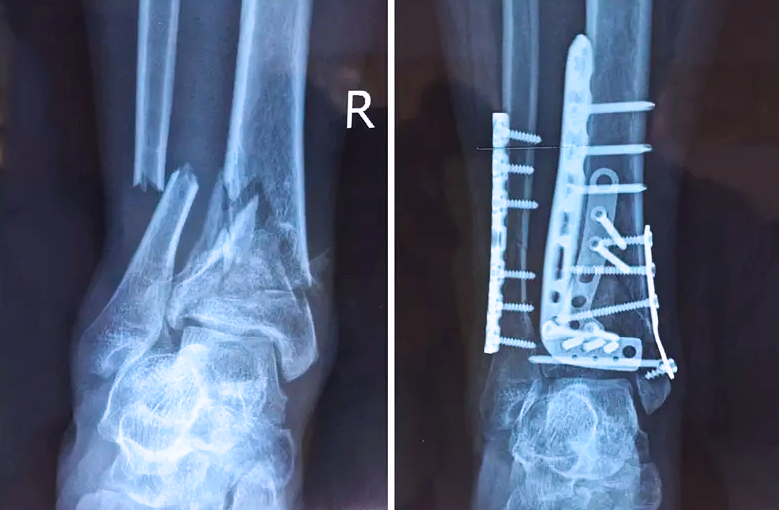

對(duì)于骨科醫(yī)生而言,關(guān)節(jié)外的骨折是相對(duì)比較簡(jiǎn)單的,因?yàn)殛P(guān)節(jié)外的骨折允許我們復(fù)位的時(shí)候有一些偏差,但是如果骨折部位在關(guān)節(jié)內(nèi),我們就不能有任何的偏差。而且關(guān)節(jié)內(nèi)的骨折是有關(guān)節(jié)面的,如果關(guān)節(jié)面不平整,就會(huì)導(dǎo)致患者以后出現(xiàn)創(chuàng)傷性關(guān)節(jié)炎等癥狀,或者出現(xiàn)長(zhǎng)時(shí)間的疼痛,甚至造成殘疾。所以對(duì)于關(guān)節(jié)內(nèi)的骨折,一定要做到“解剖復(fù)位”,就像搭積木一樣,每個(gè)積木塊、每個(gè)碎骨塊都要完好的拼到一起,做到嚴(yán)絲合縫。

踝關(guān)節(jié)是人體中負(fù)重較大的關(guān)節(jié),也是活動(dòng)度較大的地方,所以對(duì)于足踝部位的關(guān)節(jié)內(nèi)骨折,我們更需要做到“解剖復(fù)位”。對(duì)于這種關(guān)節(jié)內(nèi)的骨折,尤其是踝關(guān)節(jié)內(nèi)部的骨折,不僅需要進(jìn)行X影像平片正側(cè)位的拍攝,由于在二維影像上無法判斷關(guān)節(jié)面的受損情況,往往還需要進(jìn)行三維影像的檢查。

在術(shù)前,我們需要做三維掃描的CT檢查,我們必須要有CT的片子,還要有三維的重建。

在術(shù)中,我們?cè)趺慈ヅ袛嚓P(guān)節(jié)面平不平整呢?常規(guī)的正側(cè)位影像是不能判斷的。有些醫(yī)生為了準(zhǔn)確的判斷,可能會(huì)選擇做開放性的手術(shù),把關(guān)節(jié)暴露出來,在眼睛的直視下判斷關(guān)節(jié)面平不平整。但是關(guān)節(jié)全部打開,無疑增加了病人的創(chuàng)傷,而且增加了患者的恢復(fù)時(shí)間。所以如果在術(shù)中我們有三維影像的支持,對(duì)醫(yī)生做手術(shù)而言就會(huì)事半功倍,而且能夠大大的增加手術(shù)準(zhǔn)確度,增加患者術(shù)后的預(yù)后。所以在術(shù)中有三維影像的支持是非常必要的!

三維影像? 看透關(guān)節(jié)內(nèi)骨折的“眼睛”